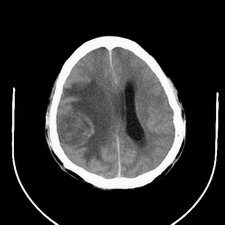

标题: CT25808:男,48岁,头痛多年,近段时间头痛加重伴步态不稳 [打印本页]

标题: CT25808:男,48岁,头痛多年,近段时间头痛加重伴步态不稳

平扫:右颞顶叶病灶呈等低密度伴大面积水肿,脑室受压变形。增强:病灶显著强化。考虑淋巴瘤或黑色素瘤。